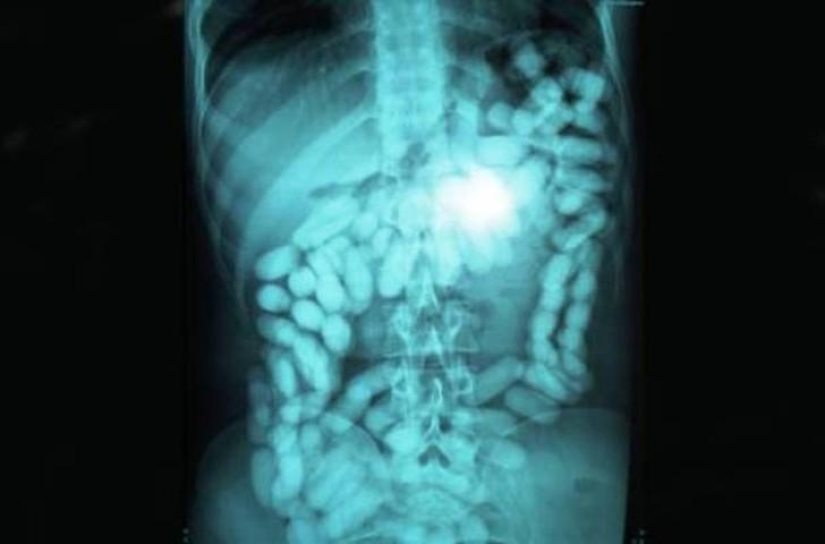

Coins.